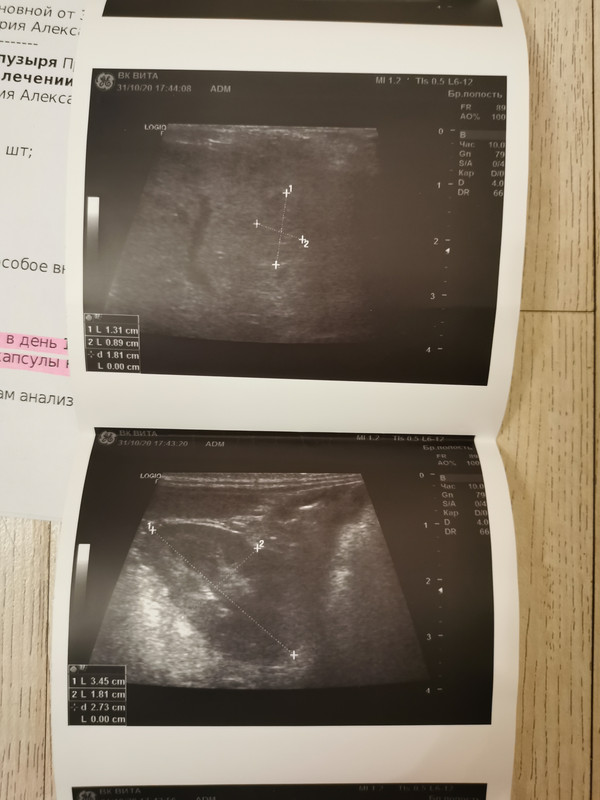

Новооброзование печени (йорк13лет)

Новооброзование печени. Йорк 13лет. Прошу помощи ветеринара гомеопата. Хочу помочь собаке.